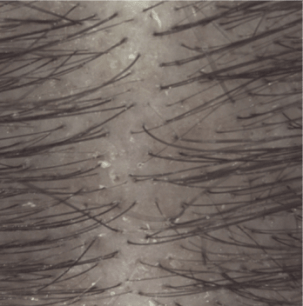

Lo shampoo KERTYOL PSO è specialmente indicato per la cura del cuoio capelluto soggetto a psoriasi.

La sua formula innovativa agisce a tutti i livelli della fisiopatologia della psoriasi. Lo shampoo trattante può essere utilizzato in associazione a trattamenti dermatologici specifici, in alternanza o come mantenimento per limitare la ricomparsa delle placche.

Risultati di efficacia

Spessore delle placche dopo 1 mese (3)